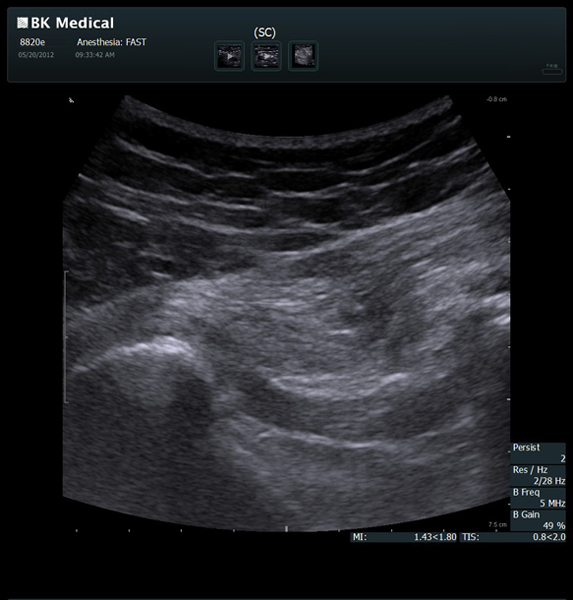

Transducers Designed for Guidance

BK Medical offers high-frequency linear transducers, imaging from 18-2 MHz for upper and lower extremities, and curved array abdominal transducer 8820e for special deep nerves or paravertebral/spinal applications. Our transducers provide superb detail that makes it easy to see your needle during procedures.